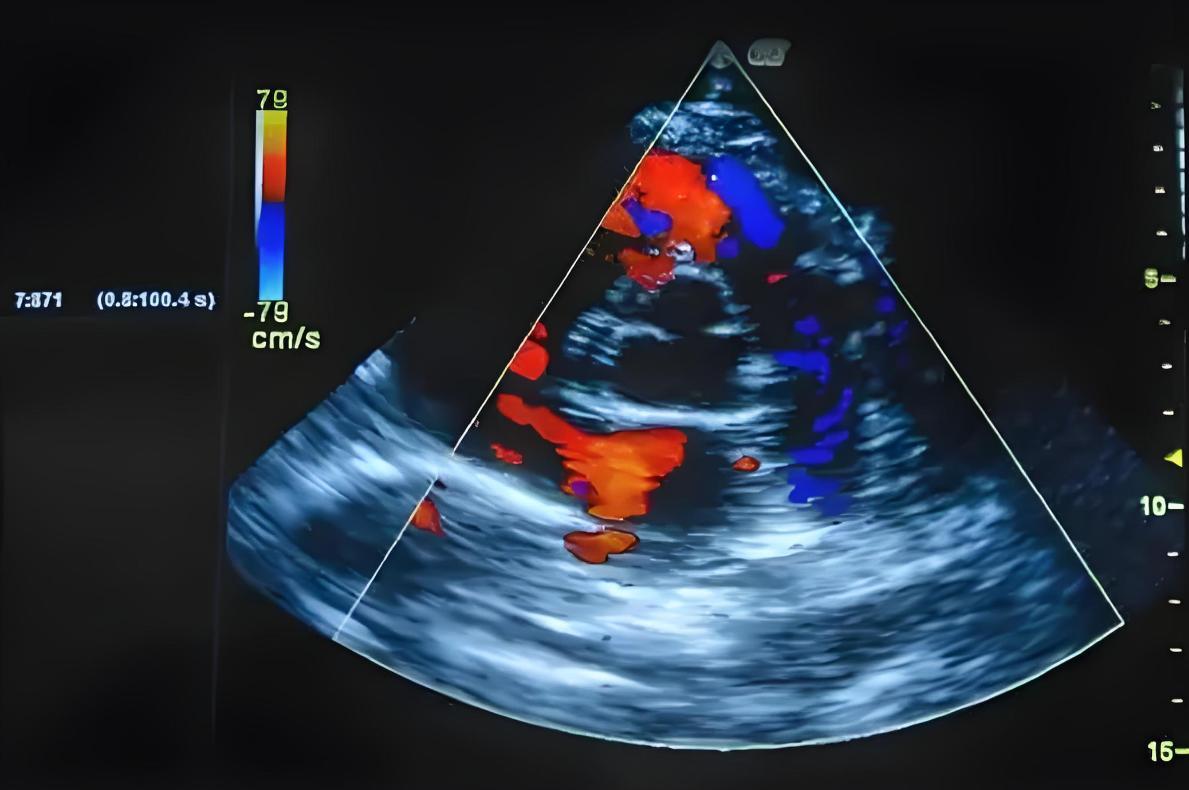

腹黑彩超:看结构、看功能

腹黑彩超是检查腹黑结构和功能的“照妖镜”。它能看到腹黑的大小、瓣膜有莫得问题、射血功能是否遍及等。

有的中老年东谈主往往气喘胸闷,不一定是肺的问题,也可能是腹黑功能减退,腹黑泵血才智变差了。

彩超里常见一个叫“左室射血分数”的观点(LVEF),惟有在50%以上,大多证实腹黑的泵血功能还可以。

如若您的彩超恶果莫得教唆腹黑扩大、瓣膜反流、心包积液等问题,那腹黑结构基本是健康的。